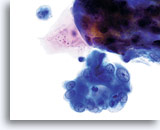

Cytologically, Type I neoplasms show atypical/malignant endometrial cells upon an increased maturation index background. By contrast, Type II neoplasms usually show upon an atrophic background. On ThinPrep samples the endometrial cells will be well preserved and may appear in 3-dimensional crowded groupings of varying sizes as well as small flat sheets containing few cells. The cells usually appear larger than their normal counterpart and the groups have smooth, sometimes scalloped borders giving them a papillary configuration. The cytoplasm is finely to discretely vacuolated and some larger vacuoles can be observed compressing the nucleus to one side of the cell as well as occasionally exhibiting polymorphonuclear cell engulfment. Nuclear features vary dependent upon the grade of the tumor. In general, as the tumor becomes less differentiated, the nucleus tends to round up with an associated gradual increase in nuclear area (µm2), size and number of nucleoli, irregularities in the distribution and coarseness of the chromatin and thickening of the nuclear membranes.

Polymorphonuclear cells may be engulfed in the cytoplasm. 60x

Overall cell size is usually larger than the normal counterpart. 60x

Nuclei “round up” compared to the normal nucleus. 60x

Nuclear membranes may be thickened. 60x

Chromatin may be clumped and irregularly distributed. 60x

Nucleoli are common and vary in frequency, size and number. 60x

Tumor diathesis and single malignant cells may be noted. 60x

Tumor diathesis may be present and appears as a “woven shroud” with a denseness or linear presentation of debris in the center and a frayed or pulled out appearance of the material around the edges of the group. 60x

Endometrial adenocarcinoma 60x